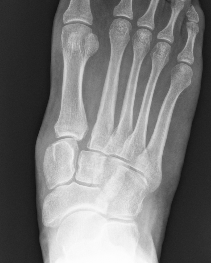

X-ray

Subtle widening of the medial cuneiform - 2nd metarsal distance, and the inter-metatarsal distance